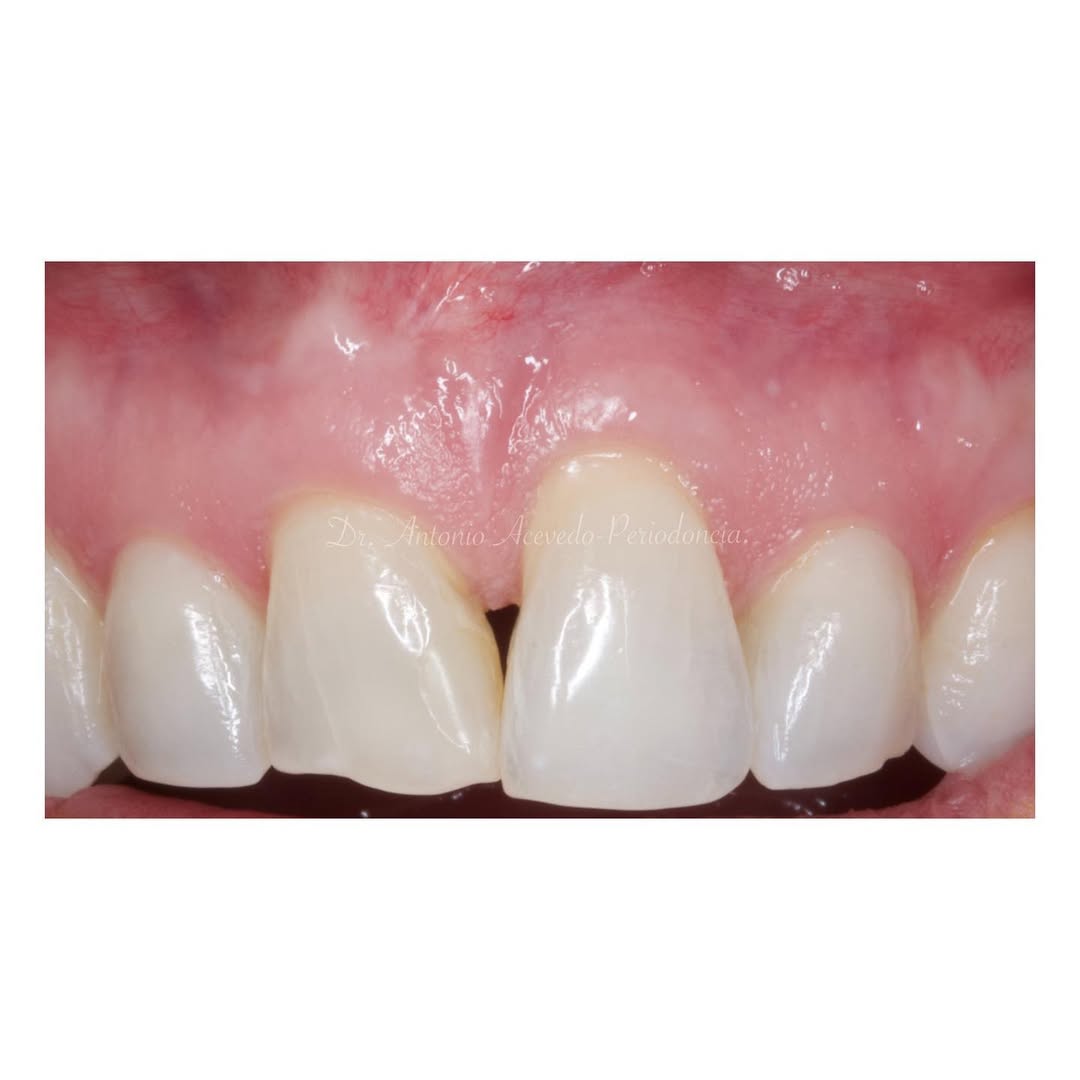

Se presenta un caso clínico de restauración directa en resina composite, ejemplo del valor de la precisión y la técnica meticulosa incluso en procedimientos considerados rutinarios dentro de la práctica diaria. El caso pone en evidencia la importancia del control de la morfología, la textura y la integración cromática, así como del adecuado aislamiento del campo operatorio y la estratificación del material, factores determinantes para conseguir un resultado natural, funcional y duradero. A través de una ejecución cuidadosa, se logró una restauración estéticamente imperceptible y funcionalmente estable, que respeta los principios de mínima invasión y adhesión efectiva. Este tipo de procedimientos, aunque cotidianos, reflejan la constancia y el nivel de exigencia clínica necesarios para ofrecer odontología de calidad en todos los casos, independientemente de su complejidad.